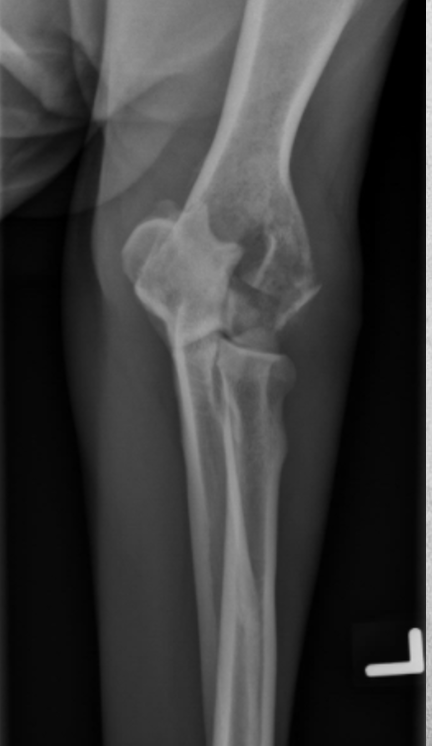

3 years old male Labrador

Progressive lameness of left front limb for 1 month

A

Osteolysis of humeral condyles and disruption of the cortex on lateral views.

Fracture line is visible on craniocaudal view, transverse across the lateral epicondyle.

Diagnosis: Aggressive neoplasia – T-cell lymphoma